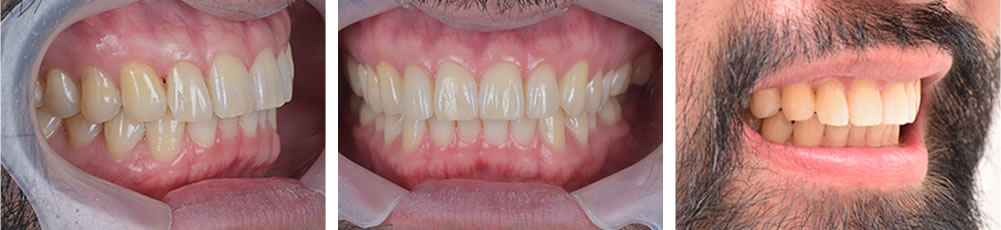

術後経過2年の口腔内写真です。歯の変色もなく、機能面、審美面ともに経過良好でした。